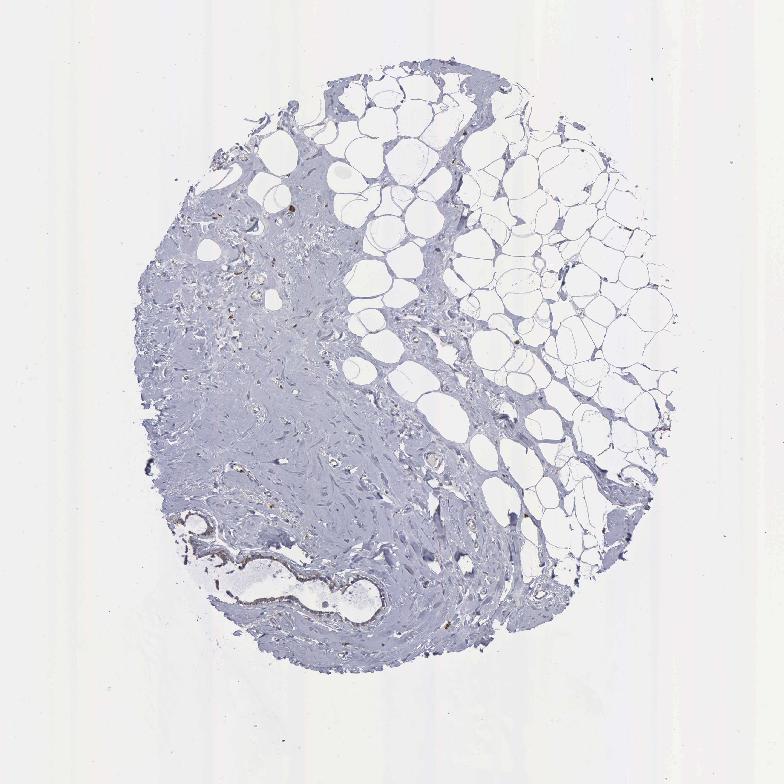

Information about each individual sample is listed below, including gender, age, a tissue section image and estimated fractions of cell types. pTPM (transcripts per million) values give a quantification of the gene abundance which is comparable between different genes and samples.

Glandular cells: 15 Adipocytes: 5 Other cell types: 80

Female, age 80

Breast sample 390 pTPM: 301.9